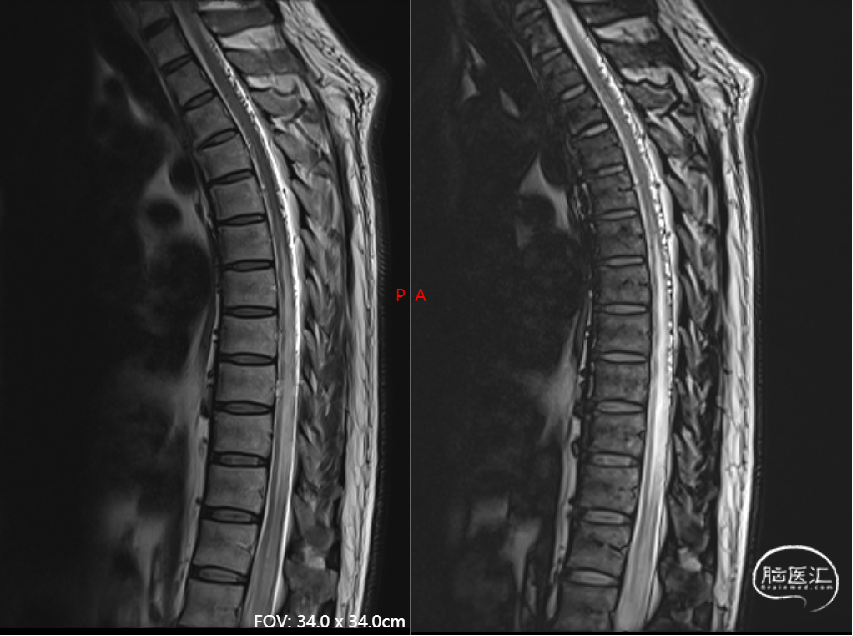

术前影像(2024-02-20, 本院)

image.png

现病史摘要:缘于5月余前患者无明显诱因逐渐出现双下肢无力,走路时酸胀感,易疲劳,不能长距离行走,右下肢明显,晨轻暮重,无疼痛、肌肉萎缩和大小便异常,完善颈胸部MRI显示胸髓表面多发迂曲血管影,胸5-12椎体水平髓内异常信号。